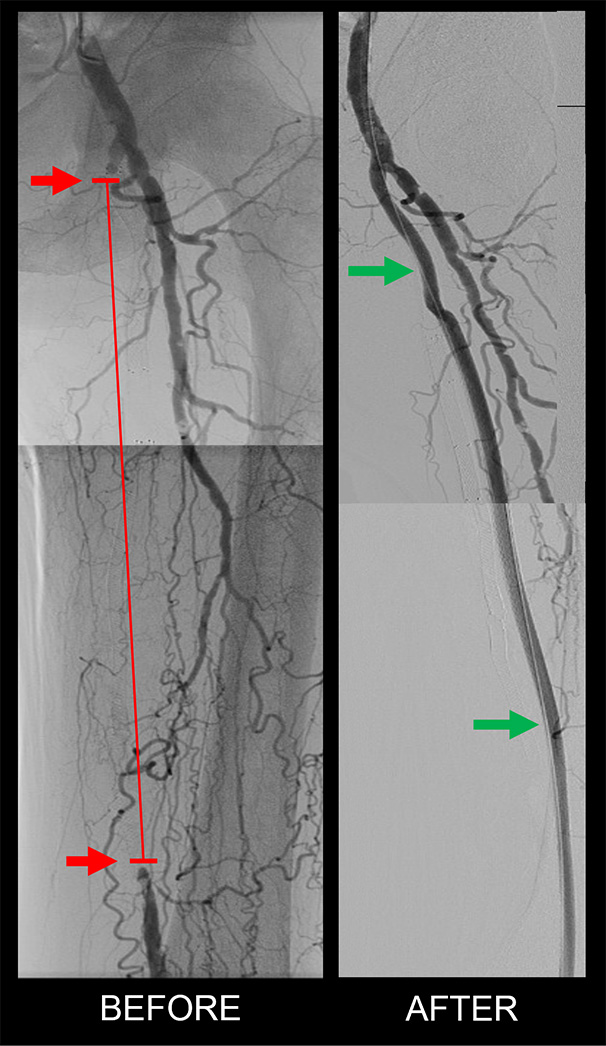

The red path highlighted on the left is indicative of where the patient has no blood flow going down their femoral artery. The image on the right shows the blood flow that has been reestablished via the DETOUR procedure, and blood is now flowing through the stent that has been placed in the femoral vein. After blood flow has been restored to the leg, patients may walk painlessly, having avoided the need for amputation.

Unlike traditional methods for treating hardened blocked arteries, including balloon angioplasty and stents--which can have a higher rate of failure--or bypass surgery requiring multiple large incisions along the leg, in this PTAB technique, a surgeon passes a stent from healthy femoral artery in the groin into the adjacent femoral vein and then re-enters into healthy popliteal artery around the knee. It’s like taking a detour in a car, when one of the outbound lanes of the interstate highway is converted to an inbound lane in case of accident or construction, before it rejoins the original inbound lane. In the leg, the outbound lane is usually double the size of the inbound lane and can easily accommodate this extra traffic.